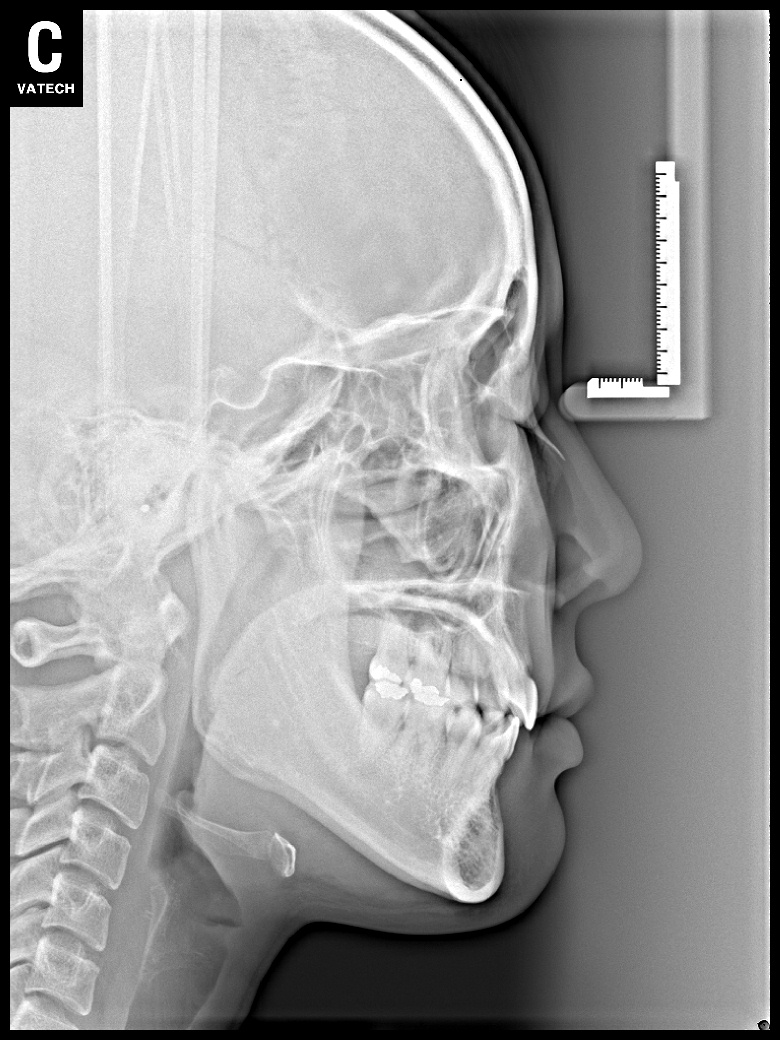

치료 전 사진입니다.